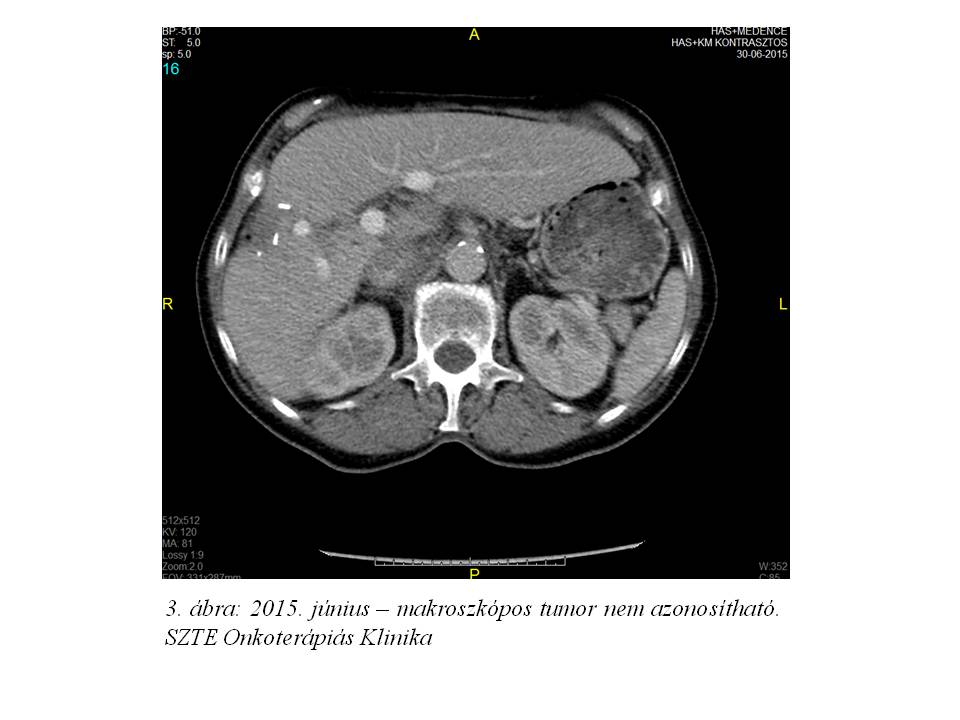

Figyelembe véve a visszatérő hematogén mellékhatást (anaemia) és azt, hogy további dózisredukcióra dózistartalék már nem állt rendelkezésre, illetve az idős beteg hallása az elmúlt időszakban jelentősen romlott (jelezve, hogy a beteg kezelése során a kumulatív cisplatindózist elértük), valamint hogy a radiológiai komplett remissziót a legutolsó képalkotó kontrollok (3. ábra) is megerősítették, a beteg kezelőorvosa a kemoterápia felfüggesztését javasolta, mellyel az intézeti onkoteam és a beteg is egyetértett.